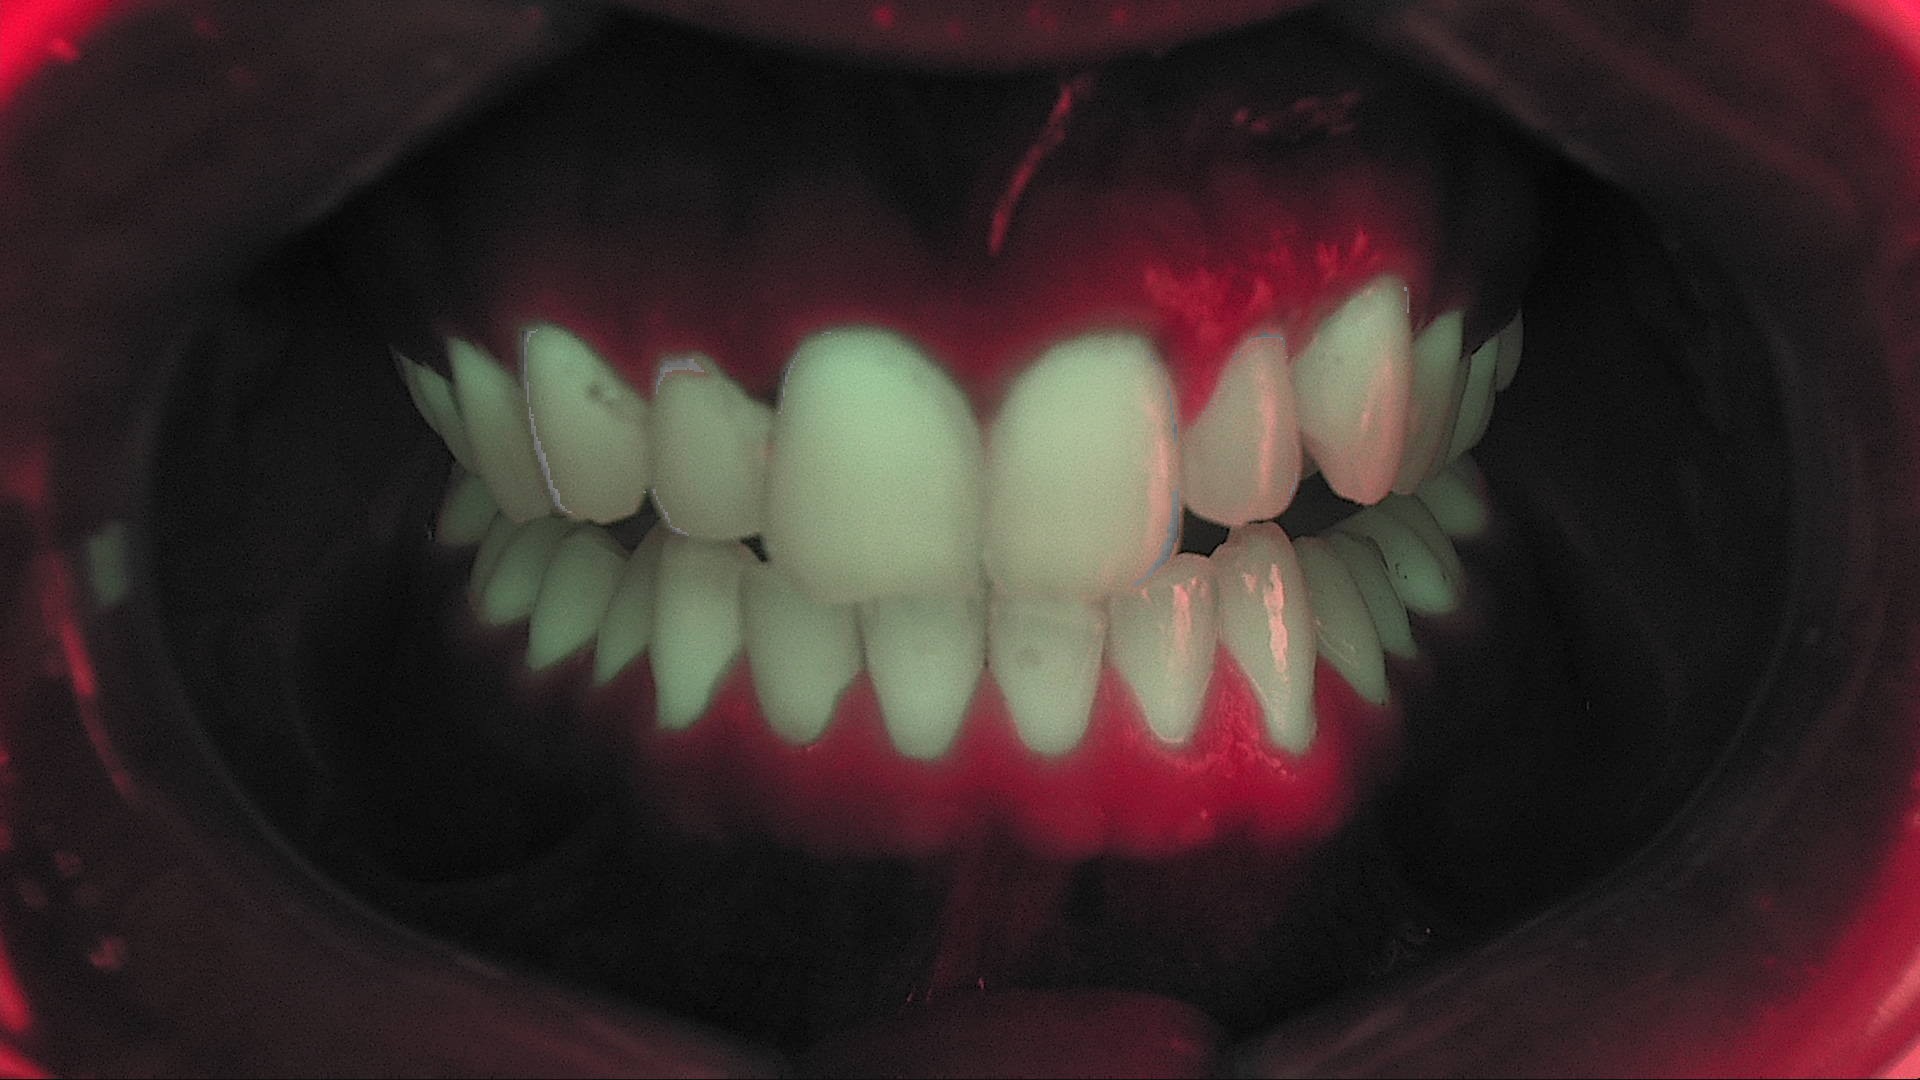

Fig. 1B - Fluorescenza pretrattamento. Valori ΔF medi intorno a –47,8%, indicativi di demineralizzazione.

Fig. 3B - Fluorescenza immediata post-trattamento: ΔF ridotto a circa –13,4%, segno di saturazione dei micro-pori.